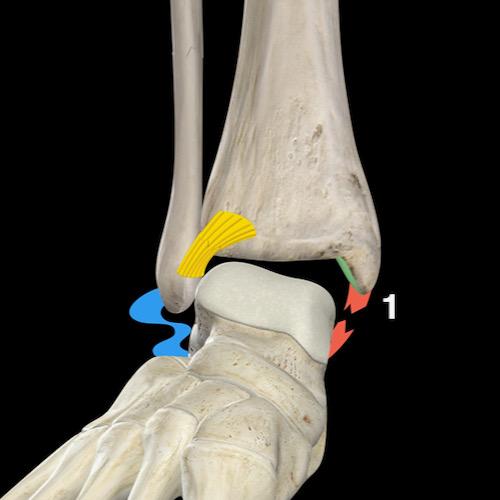

Bước 2 – Đây có phải là gãy xương Weber B / SER không?

Nếu không phải là gãy xương Weber A, câu hỏi tiếp theo cần đặt ra là: đây có phải là gãy xương Weber B không?

Khi phát hiện gãy xương Weber B — vốn luôn hiện rõ trên tư thế chụp thẳng (AP) hoặc tư thế chụp nghiêng — điều duy nhất cần kiểm tra là liệu có tổn thương giai đoạn 3 không ổn định với tổn thương phía sau, hay thậm chí giai đoạn 4 với tổn thương phía trong hay không.

Gãy xương Weber B là loại gãy xương cổ chân phổ biến nhất, chiếm 60-70% tổng số các trường hợp gãy xương cổ chân.

Cũng giống như gãy xương Weber C, đây là hậu quả của lực xoay ngoài tác động lên bàn chân.

Điểm khác biệt duy nhất là trong gãy Weber B, bàn chân ở tư thế sấp (supination) và tổn thương bắt đầu từ phía ngoài — nơi chịu lực căng — trong khi ở gãy Weber C, tổn thương bắt đầu từ phía trong do bàn chân ở tư thế ngửa (pronation).

Lauge-Hansen gọi cơ chế gãy xương này là sấp-xoay ngoài (supination exorotation – SER).

Cuộn qua các hình ảnh để thấy cách tổn thương diễn tiến theo một trình tự cố định theo chiều kim đồng hồ.

Mọi thứ trở nên rất đơn giản khi bạn ghi nhớ trình tự cố định của các tổn thương:

- Phía trước

Lực căng tại khớp chày mác trước (syndesmosis trước) gây đứt dây chằng hoặc bong điểm bám tại xương chày — gãy xương Tillaux. - Phía ngoài

Lực xoay ngoài tác động lên xương mác gây ra đường gãy chéo — gãy kiểu đẩy ra sau (push-off fracture). - Phía sau

Khi xương sên đẩy mảnh xương mác về phía sau, lực căng tại khớp chày mác sau (syndesmosis sau) sẽ gây đứt dây chằng hoặc bong mắt cá thứ ba (malleolus tertius). - Phía trong

Khi xương sên tiếp tục di chuyển ra sau ngoài, lực căng rất lớn tác động lên dây chằng bên trong (dây chằng delta) sẽ gây đứt dây chằng hoặc bong mắt cá trong.